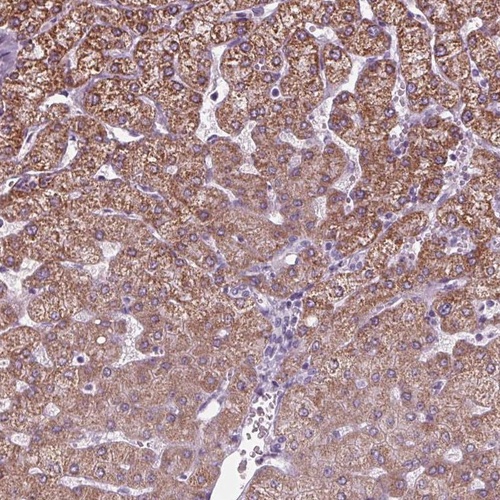

Immunohistochemical staining of human liver shows moderate cytoplasmic positivity in hepatocytes.